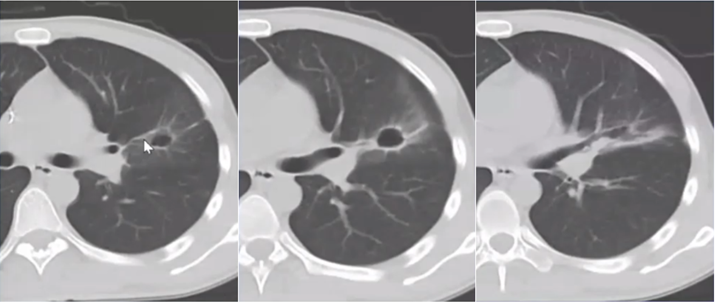

抗感染治疗后病变仍持续进展,斑片状渗出灶范围扩大,并出现实变影,纵隔窗可见密度不均匀,其中分布点状低密度灶(图3)

图片

图3  患者胸部CT(2014-07-26)

即使采取了广泛覆盖革兰氏阴性菌和阳性菌的多药联合的抗感染治疗策略,病变仍然不断进展,周围晕征不断扩大,实变成分增加,内见低密度影(图4)

图4  患者胸部CT(2014-07-31)